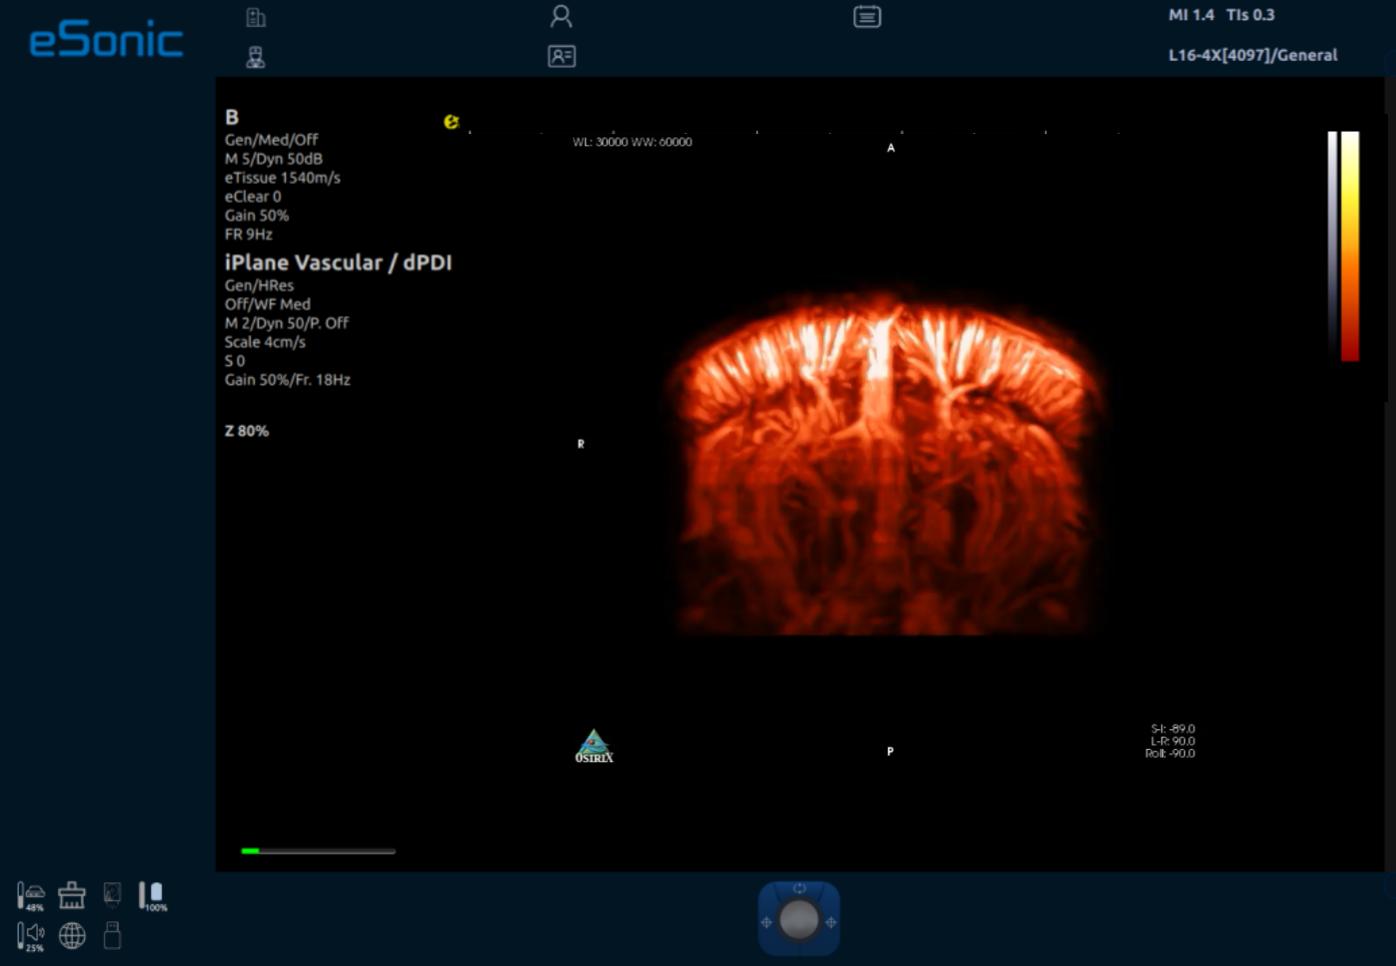

iPlane Vascular 微视血流显像-小鼠大脑皮层

iPlane Vascular 微视血流显像